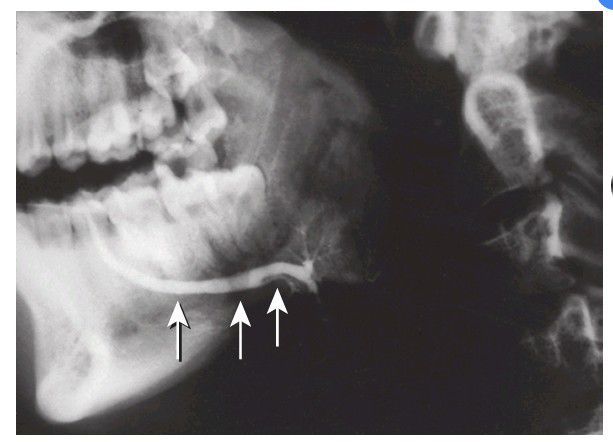

Ductal phase of a submandibular sialogram. Contrast medium is contained only within the main salivary ducts (arrows)